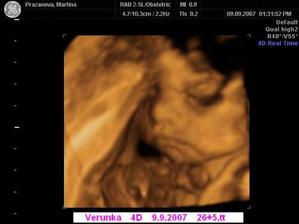

Dne 3.4.2007 to vypadá dle testů, že to vyšlo a my se snad dočkáme našeho vytouženého miminka a já nikdy nezapomenu děkovat a vážit si práce všeho personálu CAR u Apolináře. Dne 19.4.2007 nám bylo v CAR ultrazvukem potvrzeno, že opravdu čekáme naše vytoužené miminko. Dne 4.6.2007 jsme byli na genetickém UTZ ve 12+4.tt a UTZ dopadl na 1*. Dnes 26.7.2007 jsme byli na 3. ultrazvuku, jsme ve 20+2.tt a miminko je v naprostém pořádku. S maminkou už je to horši, ale snad všechno nakonec dobře dopadne. Dne 30.8.2007 jsme byli neplánovaně na 4. ultrazvuku a monitoru, protože maminka upadla na schodech, naštěstí je miminko v pořádku a neutrpělo žádnou újmu. Dnes 9.9.2007 jsme byli s tatínkem na 4D ultrazvuku v Gennetu Praha, máme krásné fotečky a DVD. Dozvěděli jsme se, že miminko v mém bříšku je holčička. Večer 9.9.2007 jsme naší holčičce vybrali jméno, je to Verunka.